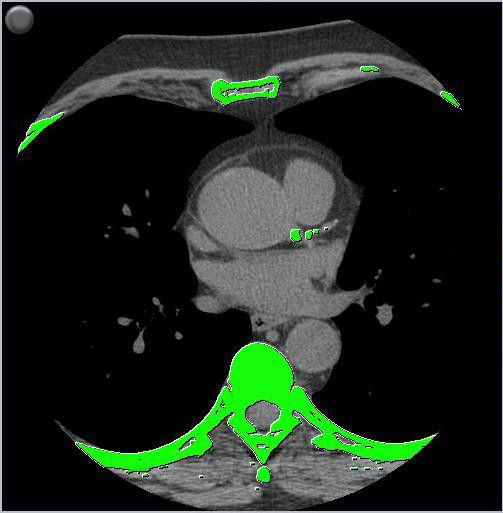

Fortschrittliche Bildgebungssoftware zur Erkennung, Quantifizierung und Bewertung von Koronarkalk. Sofort.

SmartScore 4.0 dient zur Erkennung und Messung von örtlich und insgesamt vorhandenem Koronarkalk anhand eines CT-Scans sowie zur Ermittlung von Kalkscores. Diese Werte können mit der Agatston/Janowitz (AJ)-Methode berechnet werden. Im Zusammenhang mit den persönlichen Patientendaten kann anhand dieses Werts für den Patienten eine Schätzung des Risikos für das Auftreten einer Koronararterienerkrankung abgegeben werden.

4. Erkennt automatisch Kalk und hebt ihn grün hervor